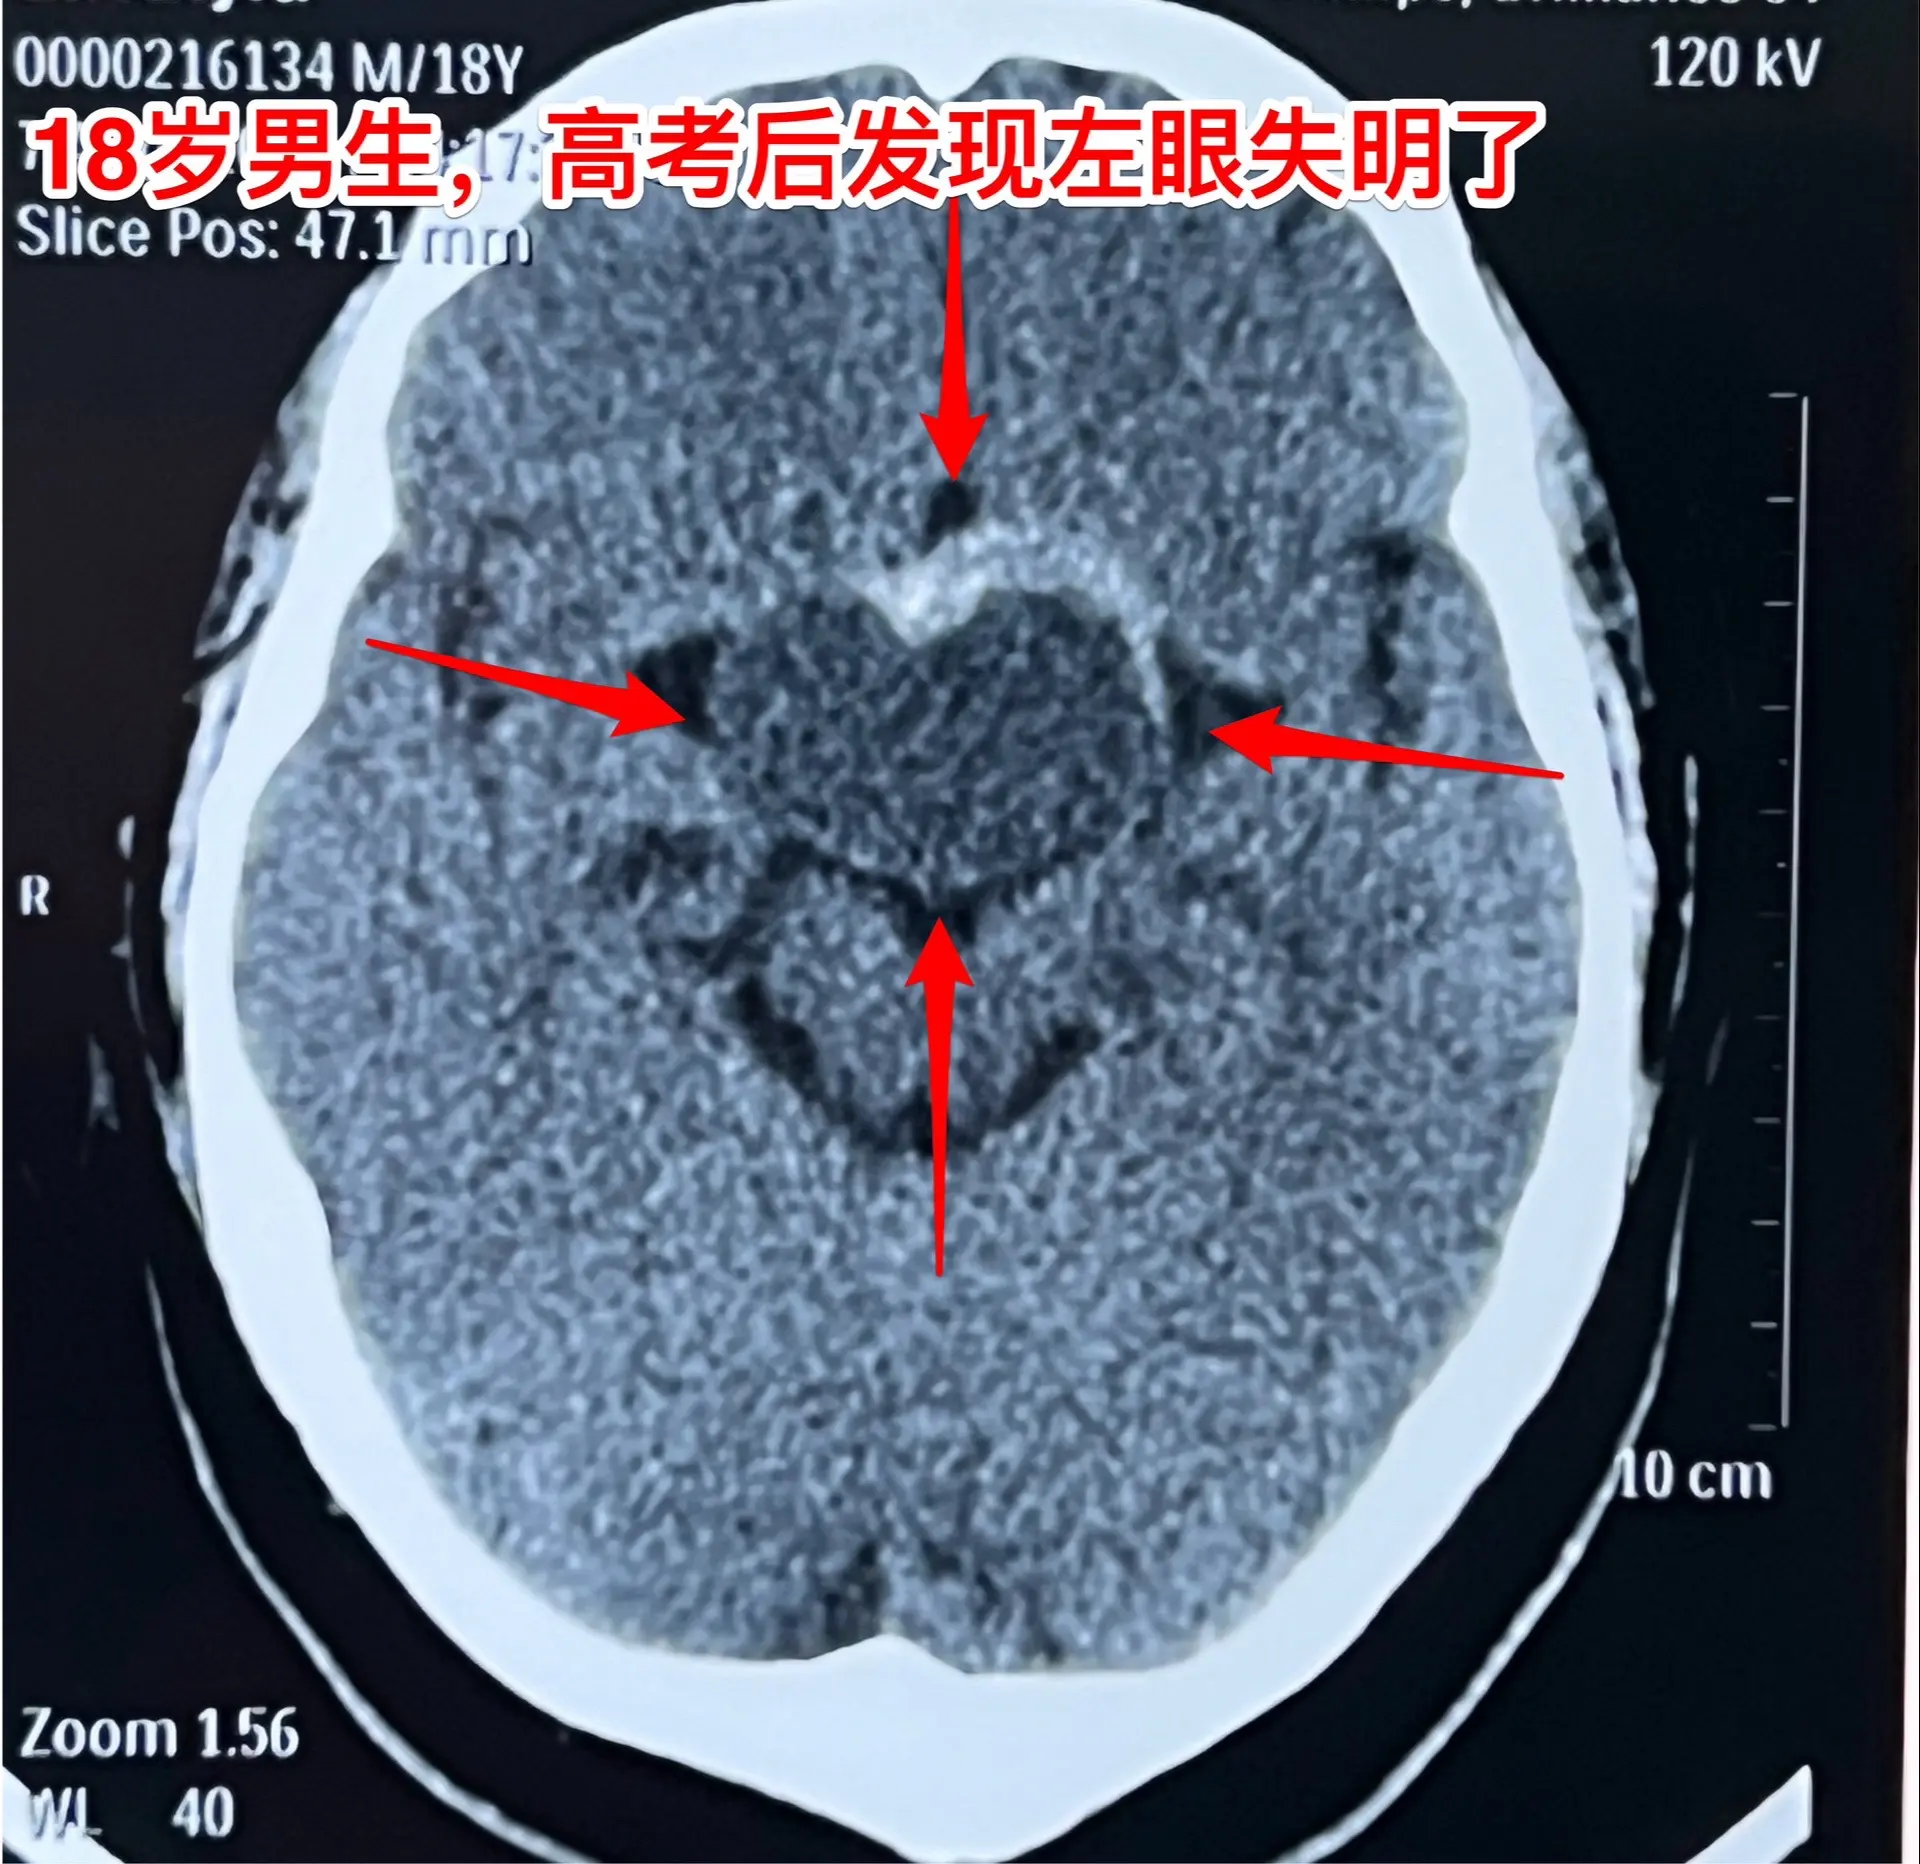

男生高考后想打工,居然发现脑部长瘤了。18岁四川男生,高考后到北京来投奔姑姑,准备到北京打工。 小伙子命苦啊,幼时父亲因病离世,母亲离家,他和奶奶一起生活、长大。 高考后小伙子到北京来投奔姑姑,准备打工,姑姑已经在北京安家了。 姑姑发现小孩子的眼睛似乎出了问题,视力不好,看手机比较困难。仔细询问,才知道他的左眼已经失明了差不多三个月了,一年多前他的右眼视力也明显下降了,这个粗心的孩子居然没有告诉家人。 到北京的医院检查,发现脑部长瘤了,见图。真是祸不单行!瘤体积不小了,小孩子除了视力差之外,精神也差。八月份住院准备做手术,作化验发现尿糖四个+,血转氨酶很高、胆红素也高。用药治疗了一段时间化验值才有好转。 直到九月二号才作手术。手术中发现这个病灶没有钙化,不是典型的颅咽管瘤。很幸运的是病灶完全切除了,而且垂体和垂体柄、下丘脑均保护完好。